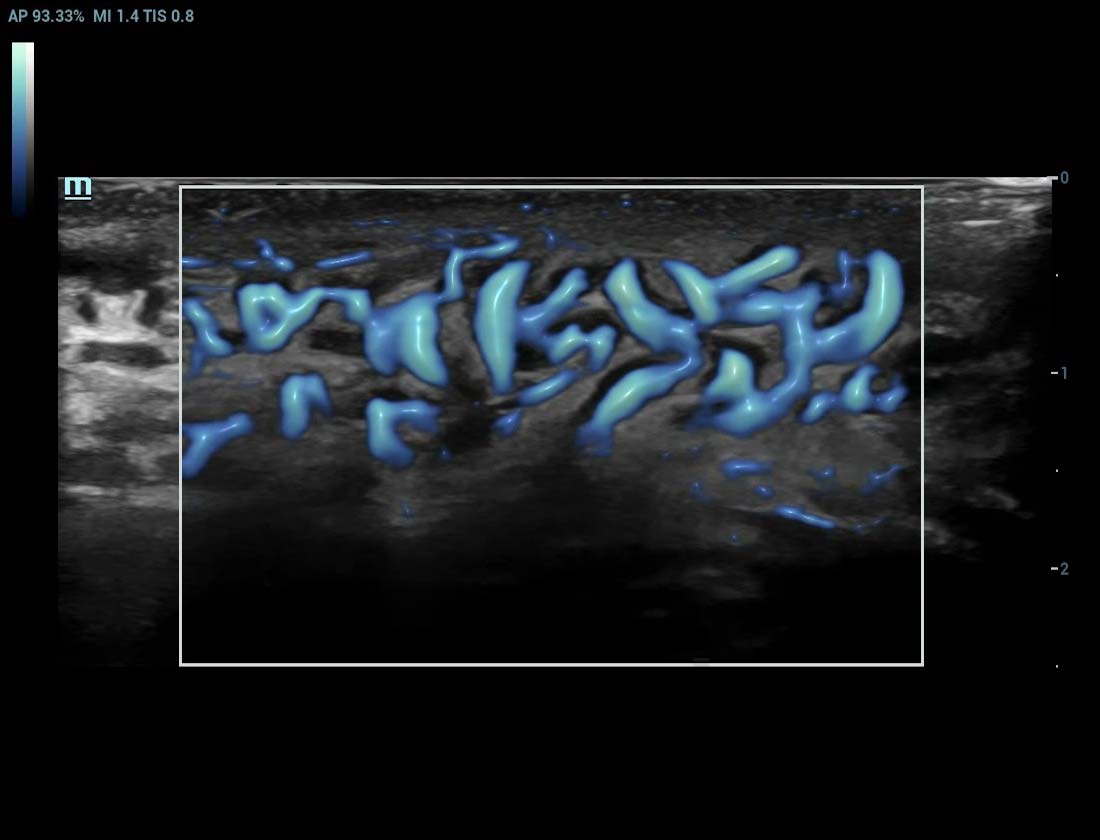

Ultra-Micro-angiografie (UMA)

UMA verbetert het diagnostische vertrouwen door de zichtbaarheid van de bloedstromen uit te breiden tot op het kleinste vaatniveau, met een superieure gevoeligheid en resolutie van de bloedstroom.

sUMA Nier

Nier PUMA